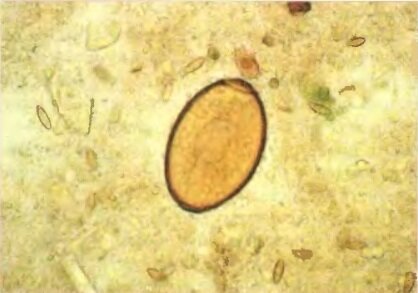

6. По окончании отстаивания предметное стекло осторожно, но быстро снять, переворачивая влажной поверхностью кверху. Во влажном слое содержатся яйца гельминтов, всплывшие в поверхностную пленку.

7. В препарат для предупреждения высыхания добавляют пипеткой 2 -3 капли водного раствора глицерина, микроскопируют.